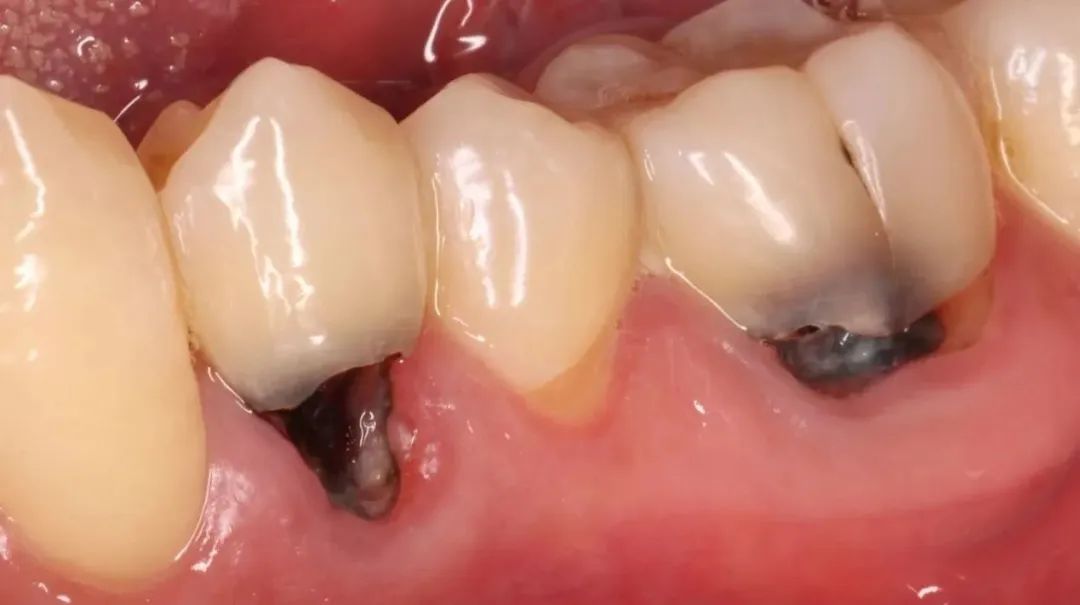

预防根面龋可采取局部用氟方法,如使用含氟牙膏刷牙,定期到医院接受牙齿涂氟等。合理膳食也很重要,控制甜食摄入总量和频率,多吃新鲜蔬菜与水果。另外需要提醒的是,出现根面龋应及时治疗。

牙周疾病是导致牙齿缺失的主要原因。如果牙齿清洁不到位,会有牙菌斑堆积,久而久之,牙龈发炎,牙槽骨吸收,牙齿松动,最终脱落。

如果老年人有牙龈红肿出血、口腔异味、牙齿松动与移位等问题,需要警惕,应及时就诊,积极治疗牙周疾病,尽量保留天然牙。